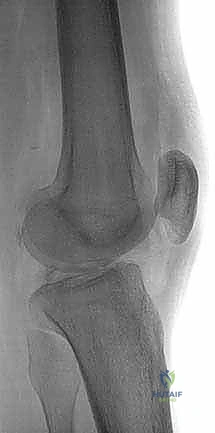

- الأشعة السينية (X-rays): لاستبعاد وجود كسور عظمية، خاصة كسور الانقلاع (Avulsion fractures) حيث ينفصل الرباط حاملاً معه قطعة من العظم.

- أشعة الرنين المغناطيسي (MRI): هو المعيار الذهبي لتأكيد التشخيص. يوضح الرنين المغناطيسي بدقة موقع التمزق، درجته، وحالة الغضاريف الهلالية والأربطة الأخرى.

- الأشعة السينية مع الضغط (Stress Radiographs): يستخدمها الدكتور هطيف أحياناً لقياس مقدار الإزاحة الخلفية بالملليمترات بدقة متناهية، مما يساعد في اتخاذ قرار الجراحة.